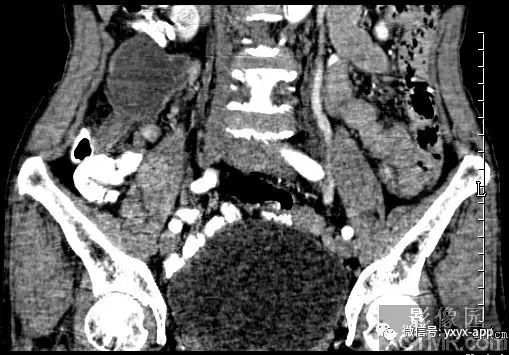

【病史临床】女性,66岁,右下腹胀痛不适一月。

CT影像表现:右下腹囊性肿块,囊液密度均匀,囊壁规整,增强囊壁有强化,周围肠腔无梗阻征象,考虑阑尾粘液囊肿或肠系膜囊肿。

最后结果:手术病理:阑尾粘液囊肿。